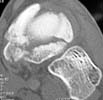

39yo male construction worker presents with 10 day old closed comminuted navicular # following low velocity fall from small motorcross bike.

Reconstruction vs. ex fix vs. primary graft and fusion.